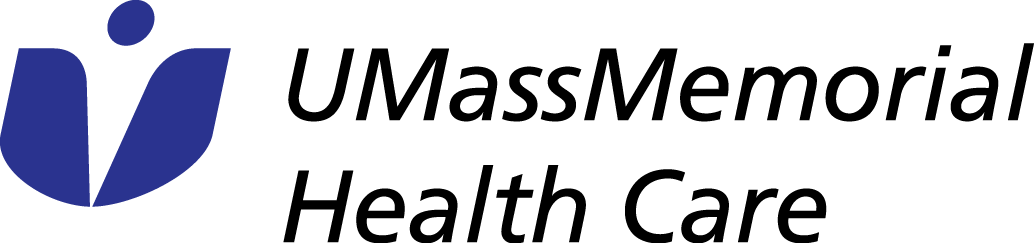

Our Nuclear Medicine and Cancer and Molecular Imaging Divisions are excited to announce the roll-out of our newest PET tracer, 18F-PSMA for prostate cancer PET/CT imaging with Shields Health Care Group. This new tracer is addressing an umet need in prostate cancer care and can detect substantially more prostate cancer lesions compared to conventional imaging. These high-quality exams are allowing us to find small sites of disease and providing clinicians with the information they need to make treatment decisions. The figures show examples of how this tracer is able to detect metastatic disease in 4 mm (left) and 6 mm (right) lymph nodes, that would otherwise not meet pathologic size criteria by CT.

Images provided by Lacey McIntosh, DO, MPH, Division Chief Oncologic and Molecular Imaging, Department of Radiology, UMass Chan Medical School.